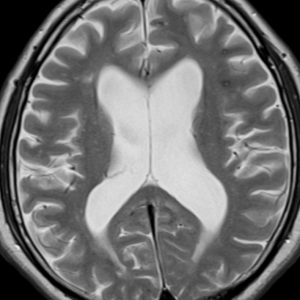

側脳室